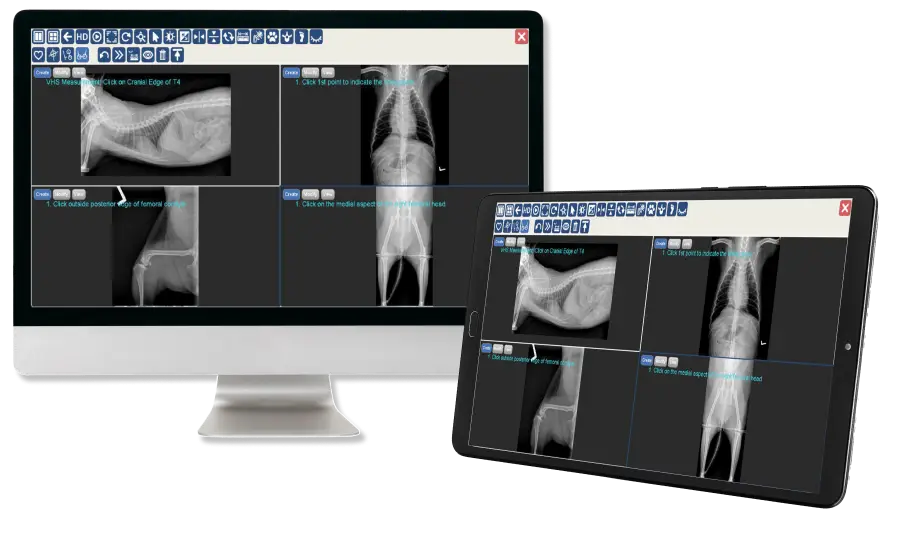

Solución móvil de procesamiento, medición, comunicación y almacenamiento de radiografía digital. Imágenes de rayos X digitales en cualquier momento y lugar.

Esta solución en la nube viene equipada con un sólido conjunto de herramientas médicas y está disponible en muchas configuraciones para las necesidades de su consulta. Los usuarios pueden ver los estudios a través de una computadora de escritorio, una computadora portátil, una tableta o un teléfono móvil.

Herramientas para Veterinaria

- Puntuación cardíaca vertebral

- Análisis de TPLO

- Análisis de TTA

- Análisis de cadera Norberg